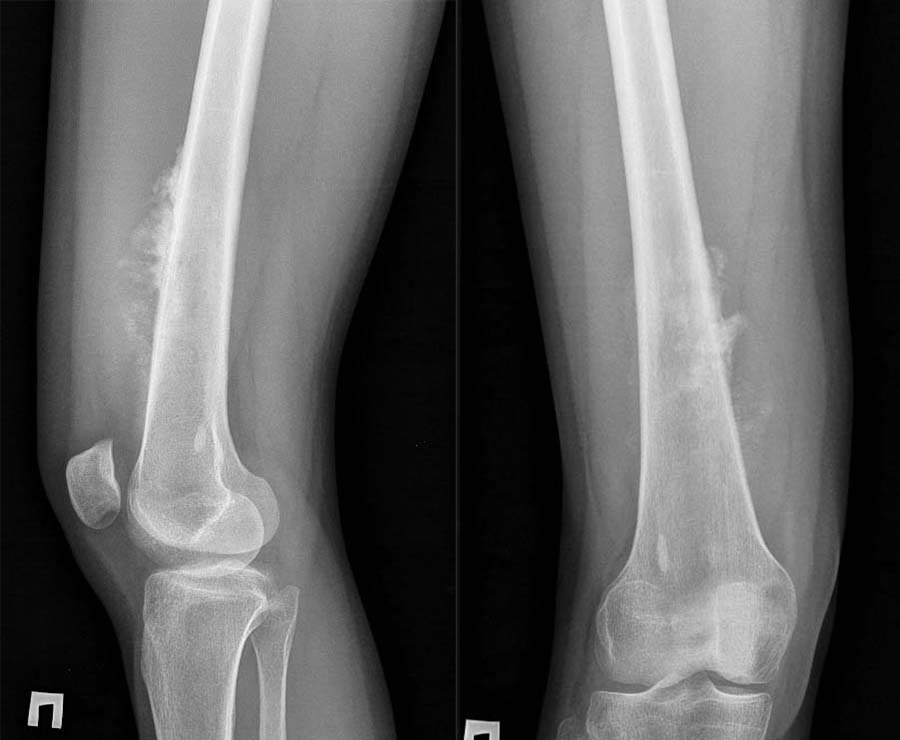

Фото: Rg при остеогенной саркоме бедренной кости

Диагностика данной патологии состоит из нескольких этапов. Первым является сбор анамнеза и истории заболевания при клиническом осмотре онколога. Затем выполнение различных лучевых методов визуализации: рентгенографии, ультразвукового исследования, компьютерной и магнитно-резонансной томографии, сцинтиграфии, а иногда и протонно-эмиссионной томографии.

Выполнение лишь одного метода визуализации не позволяет достаточно оценить данную патологию, например, рентгенография и компьютерная томография позволяют детально оценить изменение костной ткани, однако из-за специфики оптических свойств не дают полного представления о мягкотканных структурах и распространении по костномозговому каналу, что требует выполнения магнитно-резонансной томографии. Оценить распространение заболевания в целом позволяет применение различных методов радионуклидной диагностики – остеосцинтиграфии, ОФЭКТ и ПЭТ компьютерной томографии.